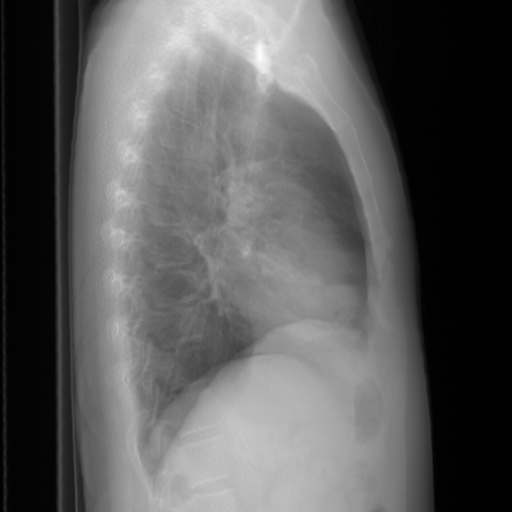

In conventional chest X-Ray exams, the erect patient is positioned between an X-Ray tube and a detector. The collected data by the detector is then used to create a comprehensive image. The main distinctions in positioning (such as anteroposterior (AP) and posteroanterior (PA), both of which we refer to a Frontal, or lateral (L)), are related to which view enables the most insight.

We compare our projected X-Rays with samples from the OpenI dataset for frontal and lateral views in Figure 5. The differences in the frontal view are due to the different positioning of the shoulder girdle. In the X-Rays, the arms are usually placed alongside the body, while in the projected images, the arms are raised due to the nature of the CT scan. In the lateral view, the X-Rays show a more comprehensive range of orientation and pose. However, the projected images, typically taken while the patient is lying down, result in similar poses between the different images. This leads to visual differences between images of female patients in both frontal and lateral views, such as the third column and second row of real X-Ray images and the first column and second row of projected images.